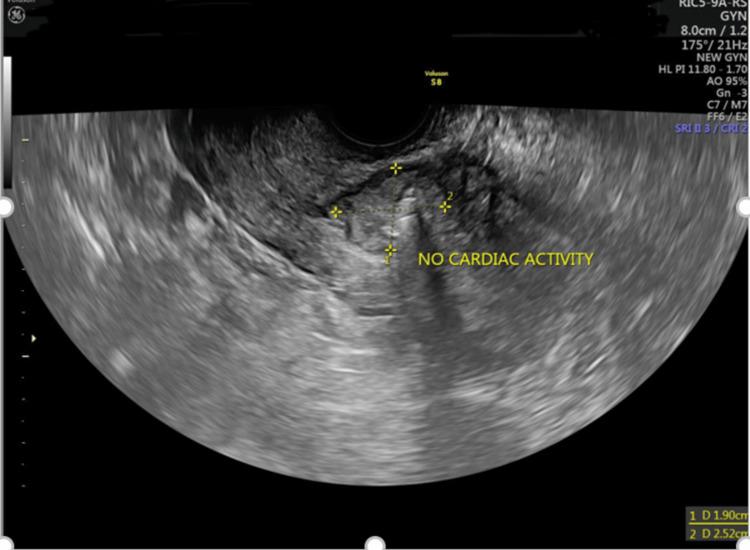

Ectopic pregnancy in the scar of a previous cesarean section contributes to significant maternal morbidity in the first trimester due to a significantly higher risk of uterine rupture if left undetected. The routine scans done in the first trimester serve as an important screening tool in the detection of such an ectopic pregnancy. Early detection can aid in making a paradigm shift from a surgical to a more conservative approach for the management of such pregnancies. Here, we report a case of a cesarean scar pregnancy diagnosed in the sixth week of gestation which was managed non-surgically with methotrexate and intracardiac potassium chloride injection.

既往剖宫产瘢痕处的异位妊娠,若未被发现,由于子宫破裂风险显著更高,会在孕早期导致严重的孕产妇发病。孕早期进行的常规扫描是检测此类异位妊娠的重要筛查工具。早期发现有助于将此类妊娠的管理模式从手术治疗转变为更保守的方法。在此,我们报告一例在妊娠六周时诊断出的剖宫产瘢痕妊娠,该病例通过甲氨蝶呤和心内注射氯化钾进行了非手术治疗。